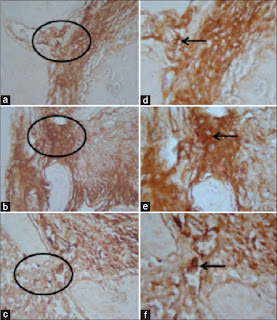

This study used 30 Wistar rats divided into three groups. In Group I, the first upper right molar tooth as healthy tooth was used for negative control group. In Group II, the first upper right molar tooth was used for a prepared root canal, and 10 ml brain heart infusion broth containing E. faecalis ATCC29212 106 CFU was injected into the canal and restored with glass-ionomer cement (GIC) for the experimentally induced chronic apical periodontitis group. In Group III, after root canal preparation, E. faecalis ATCC 29212 106 CFU was injected, and then, 10 μl propolis applied and tooth restored with GIC. It took 21 days for the periapical lesions to develop after pulp infection. The rats were then sacrificed to conduct immunohistochemical examinations in order to measure the expressions of RANKL and NFATc1.

Results:

The average of RANKL and NFATc1 expression in Group III was significantly lower than those in the experimentally induced chronic apical periodontitis group (P < 0.05).

Conclusion: